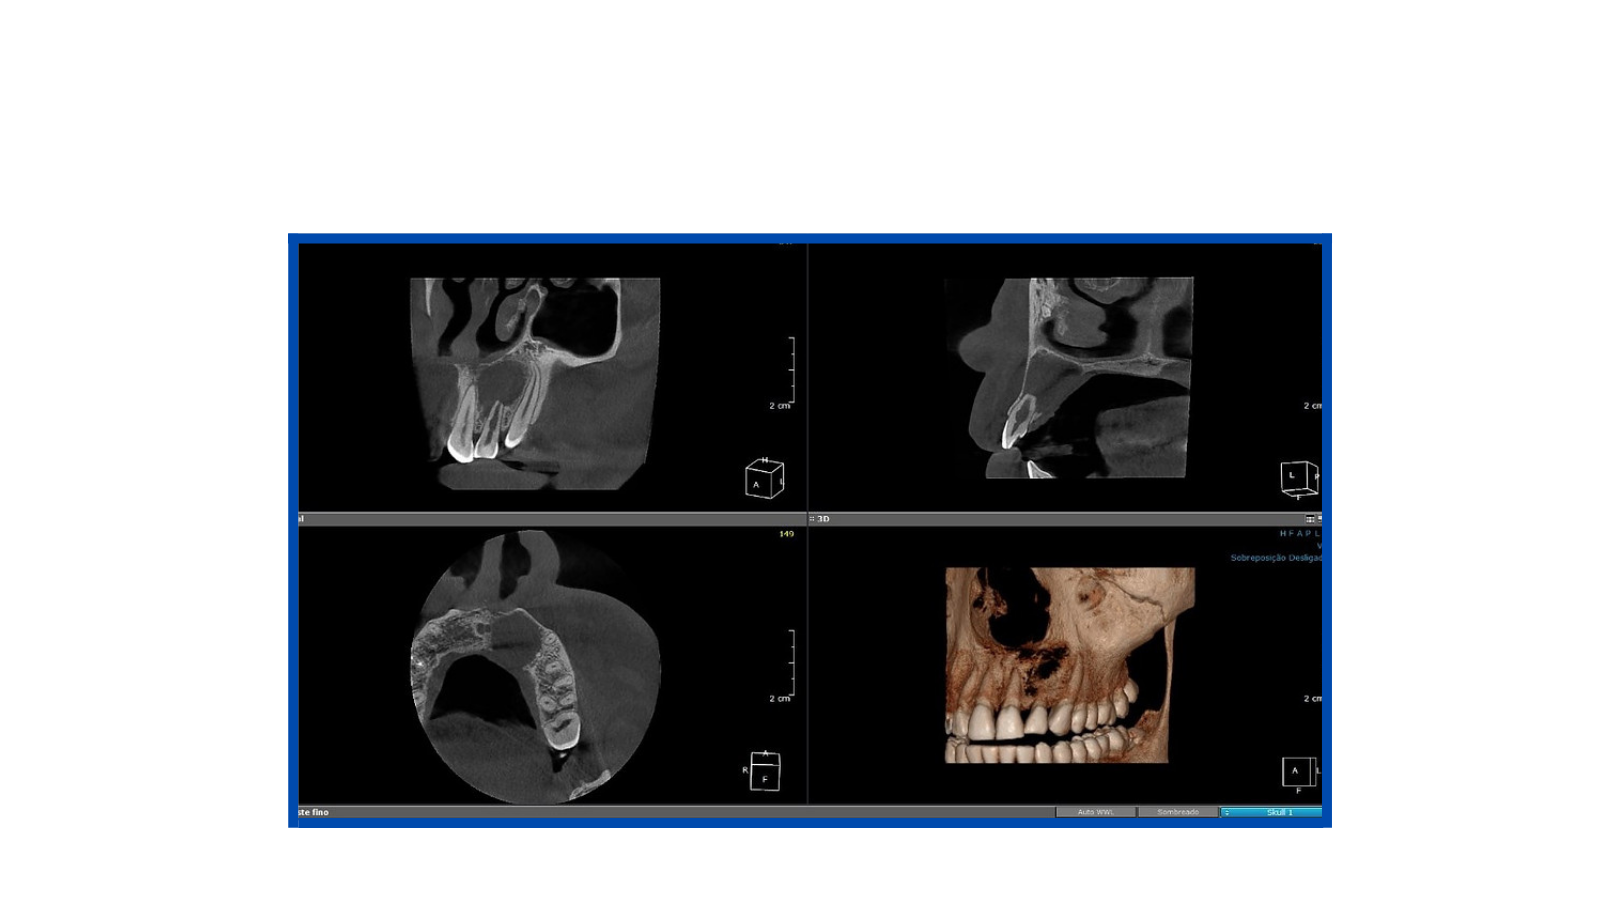

Tomografia Cone Beam

A tomografia cone beam, também chamada de tomografia computadorizada volumétrica do feixe cônico, é um exame que permite capturar imagens tridimensionais (3D) de regiões do corpo. O procedimento é usado principalmente na odontologia, pois permite visualizar as estruturas da região maxilo-mandibular com detalhes.